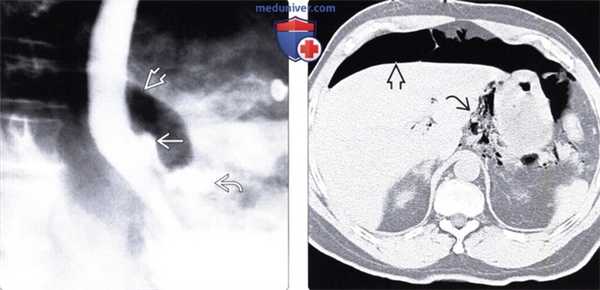

(Справа) На рентгенограмме пищевода, полученной при рентгеноскопии после введения водорастворимого контрастного вещества через назогастральный зонд, определяется утечка контраста SB через поврежденный участок в области левой передней стенки дистального отдела пищевода - типичные изменения при синдроме Бурхаве. (Слева) На аксиальной КТ с контрастным усилением, выполненной мужчине среднего возраста, предъявляющего жалобы на сильную боль в груди, появившуюся после повторной рвоты, визуализируется газ и контраст вне просвета пищевода, в окопопищеводных тканях и в нижнем средостении, верхних отделах брюшной полости.

(Справа) На рентгенограмме пищевода с водорастворимым контрастным веществом, введенном по назогастральному зонду, выполненной во время рентгеноскопии этому же пациенту, визуализируется контраст в средостении и в верхних отделах брюшной полости. Разрыв произошел в области левой передней стенки пищевода в дистальных отделах.

(Слева) На аксиальной КТ с контрастным усилением, выполненной мужчине среднего возраста, предъявляющего жалобы на сильную боль в груди, появившуюся после повторной рвоты, визуализируется газ и контраст вне просвета пищевода, в окопопищеводных тканях и в нижнем средостении, верхних отделах брюшной полости.